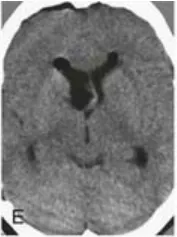

当手术顺利完成,术后CT(E)和MRI(F-H)证实,两个病灶已被完整切除。关键的是,术后没有出现任何新的神经功能或认知障碍!而术者正是巴特朗菲教授。